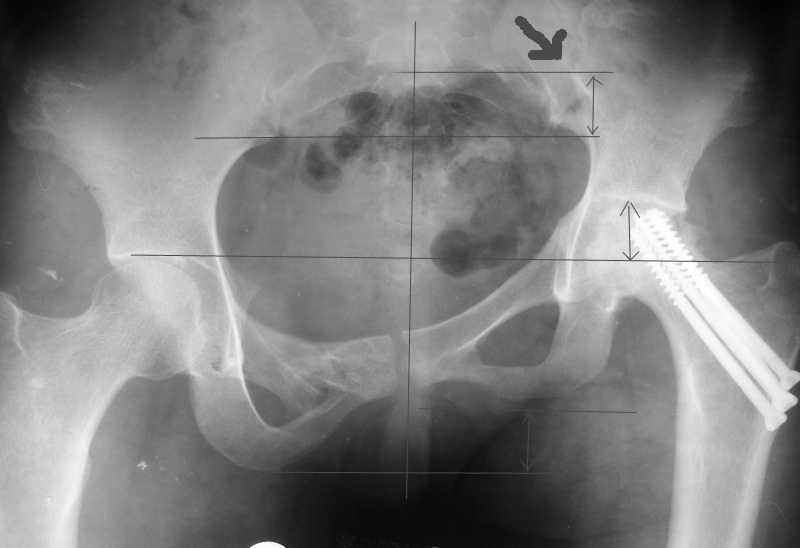

Привет, Макс. Не торопись, посмотри внимательно на истинную картину. Толстая стрелка указывает на нижний край смещенного кп сочленения.

Согласен с Рунковым. Девочка молодая. Имеется ассиметричное расположение вертлужных впадин в прямой проекции. Так как повреждение таза было вертикально-нестабильное, вероятно имеется так же ассиметрия в передне-заднем направлении. Конечно протезом можно компенсировать имеющееся укорочение, но ассиметрично расположенные тазобедренные суставы приведут к нарушению двигательного стереотипа, нарушение походки, остеохондроз и т.д.

разговоров нет, смещение значимое, какое оно было, такое и осталось. Будут проблемы и с сидением и с осанкой и т.д. Идеальным вариантом было бы, конечно, исправить деформацию, а потом запротезировать. Но... цена вопроса. сейчас деформация, судя по костной мозоли, стабильная, и таз несет основную свою функцию - опорную, явно КПС не болит. Превратить стабильную деформацию в нестабильную и потом ее исправить - задача непростая, но выполнимая. Оперативное лечение будет сложное, скорее всего многоэтапное и длительное. С определенными рисками, общехирургическими и специфическими, например несращение зоны остеотомий - нестабильный таз, ризидуальное смещение (в пределах 1 см вполне вероятно). Если считать, что на тазе укорочение см 3, остальные 5. все-таки сгибательно-приводящая контрактура. На протезе от контрактуры можно избавиться, да и см 2 удлинить за счет опила, головки. В такой ситуации решение должна принять пациентка и оно должно быть действительно информированным.